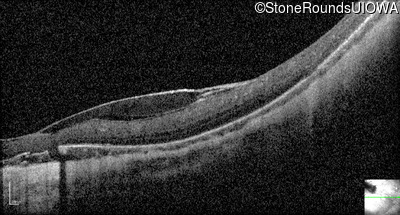

Visit at age: 13 years (Visit 2)

Optical Coherence Tomography - Right - 20/500

Exemplar / OCT Stack